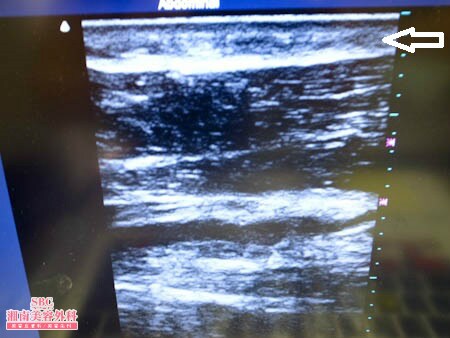

No.134541【脂肪吸引】日本人初!ライポマティック認定医であるあの有名な根こそぎ竹田先生の劇的ビフォーアフター!〜大阪から全身脂肪吸引を受けに来る!右二の腕術中3Dタッチビュー〜